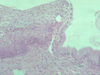

what does the endocervix normally look like histologically?

what does the squamo-columnar junction look like histologically?